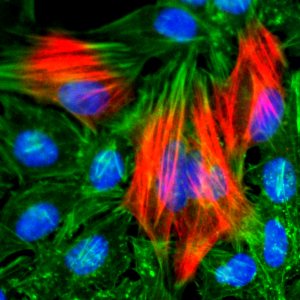

Figure 1: Formalin-fixed, paraffin-embedded human Urothelial Carcinoma stained with p21 Rabbit Recombinant Monoclonal Antibody (CIP1/2275R).